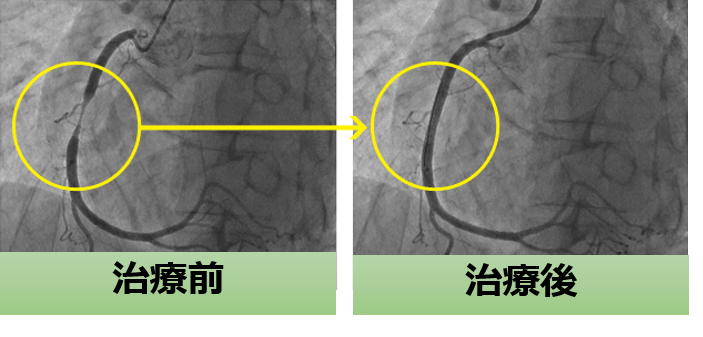

胸痛の原因は?平塚市の一般内科・循環器内科・心臓血管内科湘南いいだハートクリニック。